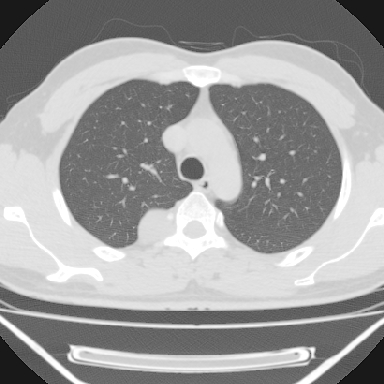

标题: CT6237:右上后纵隔旁肿块影

m 30 右胸痛10年

右上后纵隔脊柱旁类圆形肿块,边界光整,与胸腔呈钝角,首先考虑来源于肺外,神经源性肿瘤(神经鞘瘤可能大,神经鞘瘤)

右上后纵隔旁软组织肿块影,与肺界面光滑,与胸壁呈钝角相交,提示肺外病变。位于肋骨下缘,边缘清楚,呈三角样指向与右侧椎间孔,但并示进入椎间孔;与对侧神经根对比,属同一走行方向。

考虑后纵膈良性肿瘤,神经源性肿瘤可能大。

鉴别:胸膜来源肿瘤。影像表现虽有肺外征象,但无胸水等相应佐证;再者,病史前10年,超长,与胸膜肿瘤不太吻合。

右上后纵隔脊柱旁类圆形肿块,边界光整,与胸腔呈钝角,首先考虑来源于纵膈,神经源性肿瘤可能大。

右上后纵隔脊柱旁见长椭圆形肿块,边界光整,与胸壁呈钝角。周围骨质未见异常。

考虑、1、后纵隔神经源性肿瘤;

2、不除外单发胸膜间皮瘤。